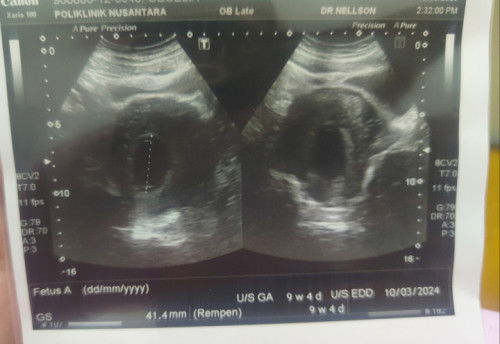

Rasenya kejadian Blighted Ovum... sy pernah alami... dimana kndungan sudah 9w+ tapi kosong je.. smp la 12w2d, kantung gugur sendiri....